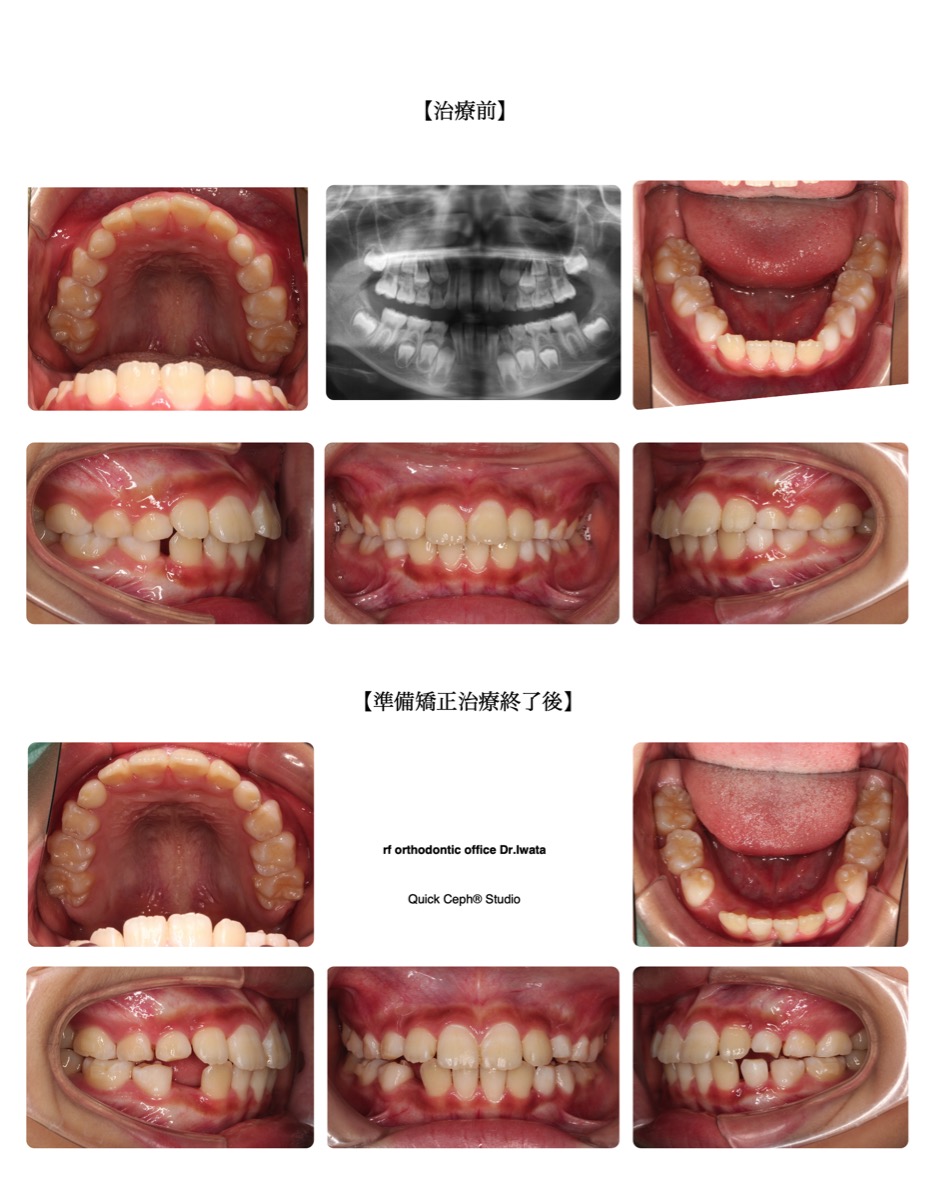

【主訴】右下の乳歯が早めに抜けて永久歯が出てくるスペースが無いと歯医者さんで指摘された。

【主な症状】叢生